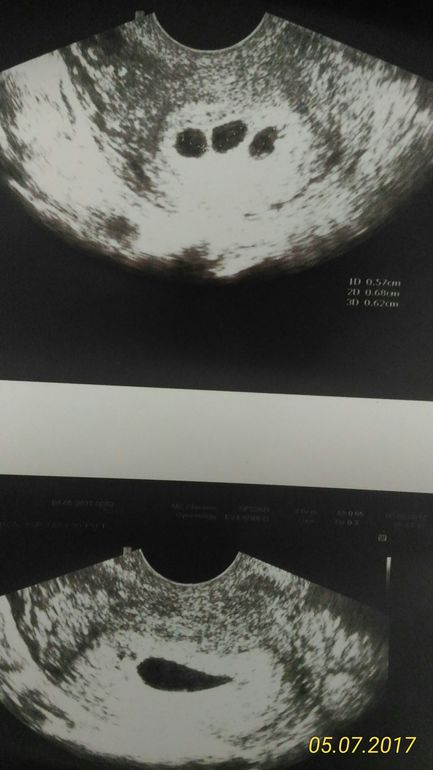

Анализы, скринингиДевочки, добрый день. У кого был пузырный занос, посмотрите мое узи. У меня 7,5 недель. Внизу - пустое плодное яйцо 12мм, вверху - еще 3 образования по 6 мм. Узист предложила подождать с чисткой, вдруг это плодные яйца. Другой врач прогнозируетпузырный занос.

Ну в одном который посредине из трёх точно не пусто?или только я вижу,как-будто желточный мешок,круглый

А они могут определить что это?у меня подруга без всякой чистки обошлась,само все вышло.ей врач говорил,она отменила всю поддержку прогестерона,может ещё что пила,не знаю,но в жк её тоже на чистку отправляли.Уже кричали,что скорую вызывают.Но у вас даже внизу пя,оно не на 7 недель.12 мм-посмотрите в таблице.Может позже все было,но как бы должен быть хотя бы желточный мешок,но те три сверху,там одно-два точно с чем-то и вообще три сверху это где?в матке?или в яичнике?

У меня был ПЗ, На картинке было множество пузырей как виноград. То,что у вас в них пусто это уже плохо, срок большой. Но как-то маловато пузырей вроде для ПЗ может просто анэмбриония. А с другой стороны, откуда столько пузырей... по гистологии уже только поймете